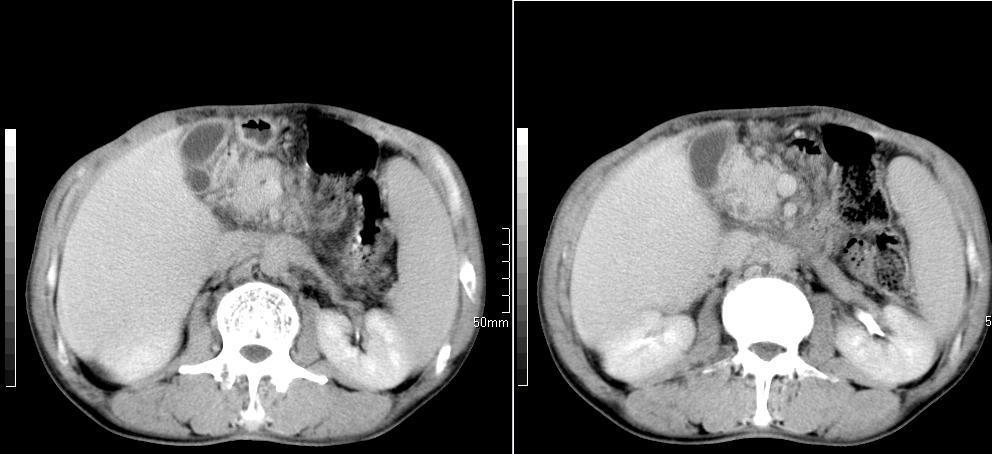

标题: CT26769:男,58岁,腹胀、腹部不适一年余 [打印本页]

标题: CT26769:男,58岁,腹胀、腹部不适一年余

肠系膜脂膜炎,胆囊炎,脾大。建议结合临床。鉴别:慢性胰腺炎并假囊肿形成。

1 慢性胰腺炎并假囊肿形成。2 慢性胆囊炎并累及肝边缘!

1)考虑慢性胰腺炎并假性囊肿形成。2) 慢性胆囊炎。3)肝内胆管扩张。

1肝内胆管扩张,性质待定,2慢性胰腺炎胰管扩张,胰腺颈部假囊肿,3肝左叶低密度为小囊肿,4胆囊炎。